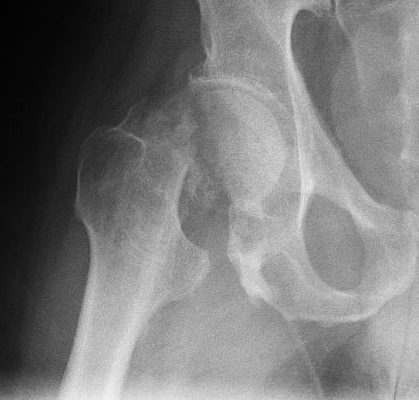

• шейка бедра.

Как упоминалось выше, такие переломы костей возникают в результате ударов малой силы, таких как падение с небольшой высоты. В некоторых случаях человек, получивший такую ​​травму, может даже не подозревать об этом. Например, перелом позвонка может не вызывать никаких симптомов — боль появляется только при повреждении нескольких соседних позвонков.

Патологический перелом диагностируется на основании жалоб пациента, осмотра и характера травмы — если к кости было приложено небольшое усилие.

Важны результаты рентгенологического исследования. Компьютерная томография и магнитно-резонансная томография (МРТ) также могут оценить состояние ваших костей и окружающих тканей. Во время этих тестов можно наблюдать изменения, которые делают возможным образование патологического перелома.